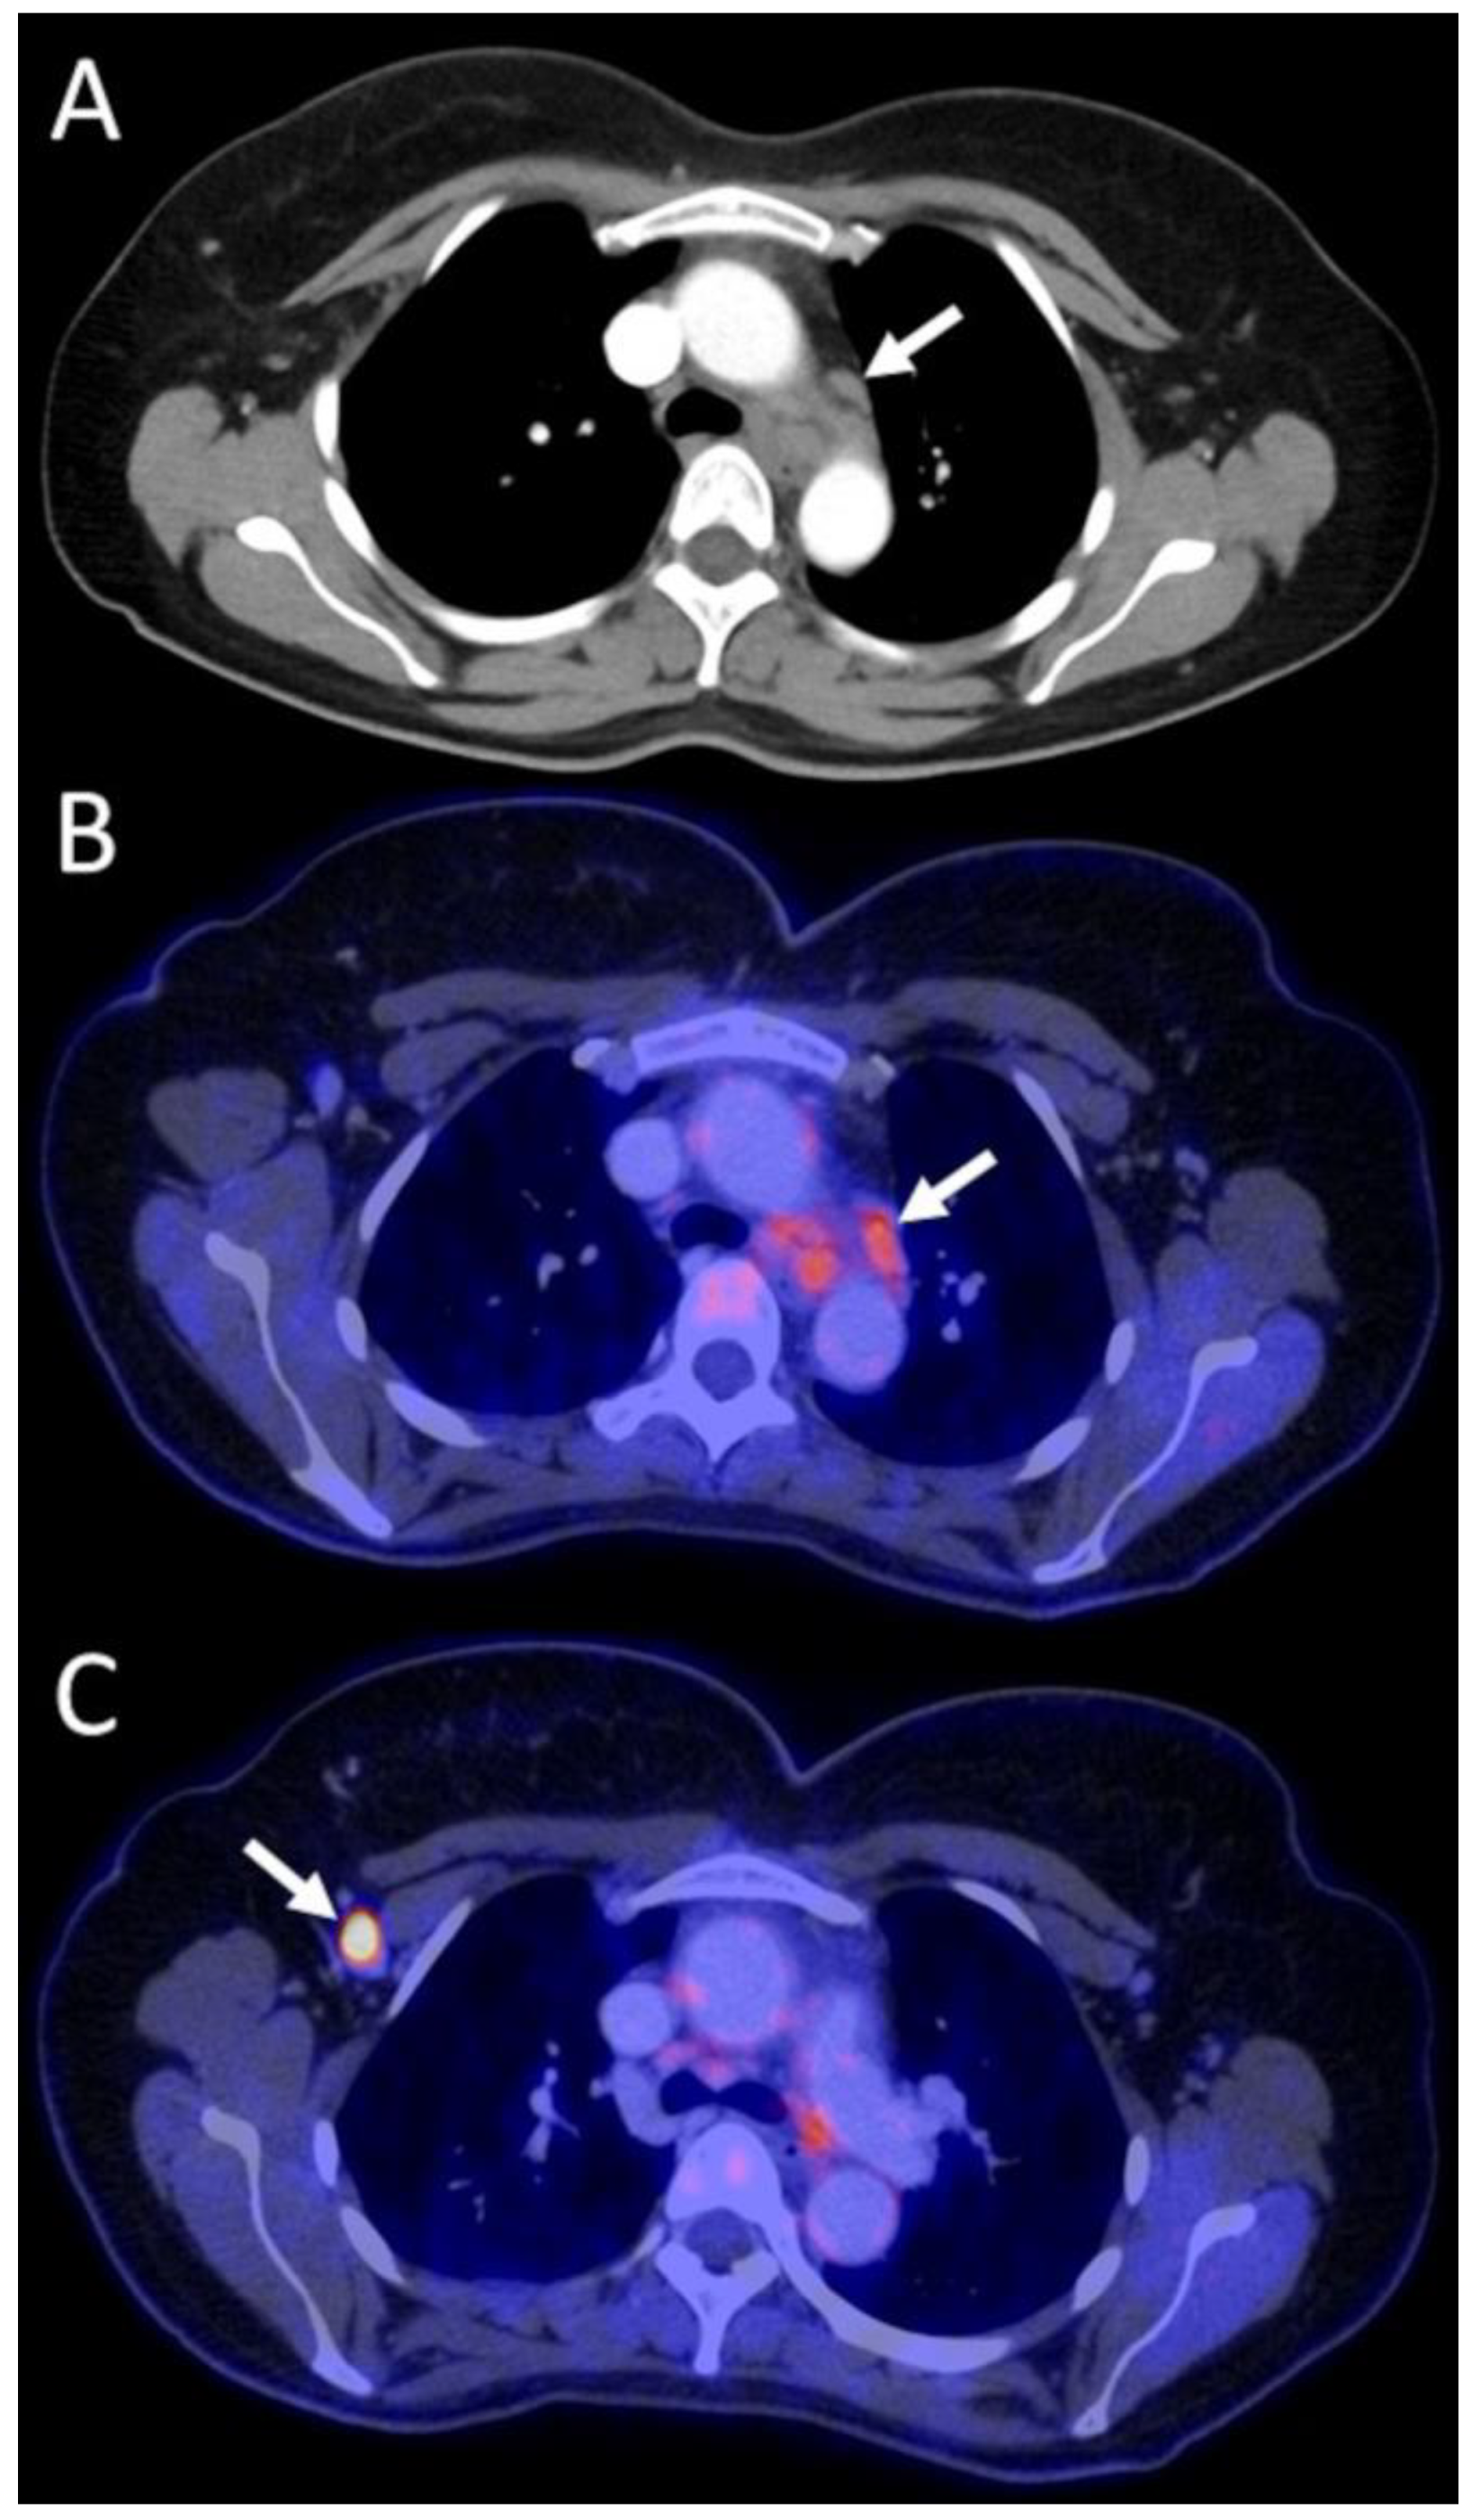

3.4.1. Primary Staging Patients (n = 15/52)

3.4.2. Restaging Patients (n = 17/52)

3.4.3. Recurrence Patients (n = 20/52)